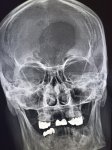

IMG20251016095819.jpg

Здравствуй двачик! Тут все мои друзья, потому бущем вместе с вами играть в доктора. Я буду постить фоточки а вы угадывать пиздецомы.

Откололась пломба, оказалось под ней кариес был, пришлось зуб депульпировать 13 к отдал за ремонт печальное это.

>>325598813

что за пятно в мозге?

>>325598844

Это дырка в кости же

>>325598580 (OP)

image